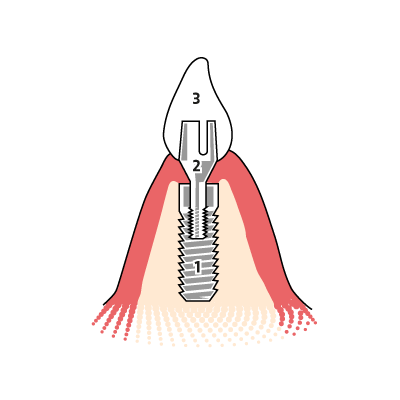

Aufbau eines Implantats